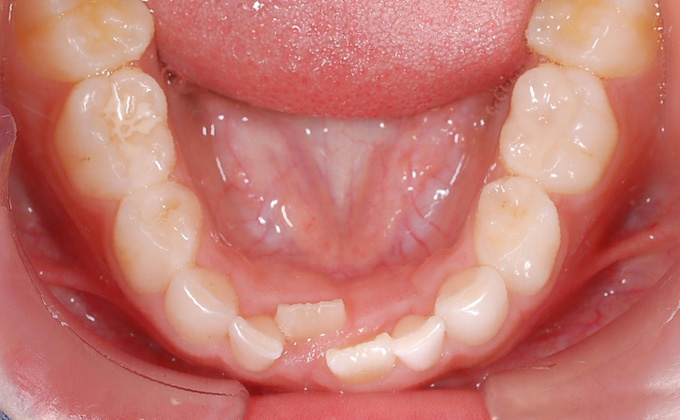

叢生(そうせい)

八重歯・乱ぐい歯など、歯が重なり合っている状態を言います。叢生の場合、歯ブラシが届かず汚れが残りやすくなります。